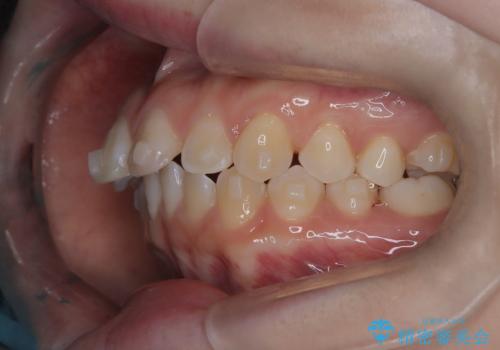

- 前歯のデコボコ(叢生)を気にされてご来院されました。精密な検査の結果、歯が並ぶスペースが不足していることが判明。患者様のご希望から、透明で目立ちにくいインビザライン(マウスピース矯正)による治療計画を立案しました。抜歯を避け、奥歯全体を奥へ動かす遠心移動という方法でスペースを確保し、前歯の叢生を解消することを目指します。

今回の矯正治療では、透明なマウスピース型の装置インビザラインを使用しました。この装置は取り外し可能で、日常生活で目立ちません。治療は、緻密に計算された計画に基づき、段階的に作製されたマウスピースを交換していくことで、奥歯から順に全体を後方へ移動させる遠心移動を実施。これにより、前歯を並べるための十分なスペースが確保され、デコボコが解消されました。抜歯することなく、機能的にも審美的にも整った美しい歯並びを獲得していただけました。